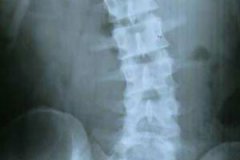

腰椎间盘突出主要是由外因、内因、椎间盘本身退行性变等原因而导致的,腰椎间盘突出给患者带来了很大的困扰。那么,腰椎间盘突出症的治疗方法有哪些呢?下面我们一起来了解。[详情]